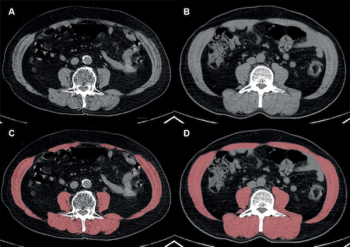

A high intermuscular adipose index has a 49 percent increased likelihood of being associated with lower overall survival in patients with resectable non-small cell lung cancer (NSCLC), according to new research.

For those without low skeletal muscle mass on CT and myosteatosis, obese patients have a 23 percent lower risk of death than non-obese patients after undergoing curative resection for non-small cell lung cancer, according to newly published research.